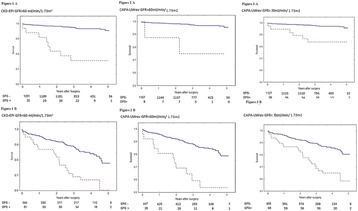

P204 - Comparison of estimated glomerular filtration rate calculated by mdrd, ckd-epi-serum-creatinine and ckd-epi-cystatin-c in adult critically ill patients

H. R. De Geus, A. Hana